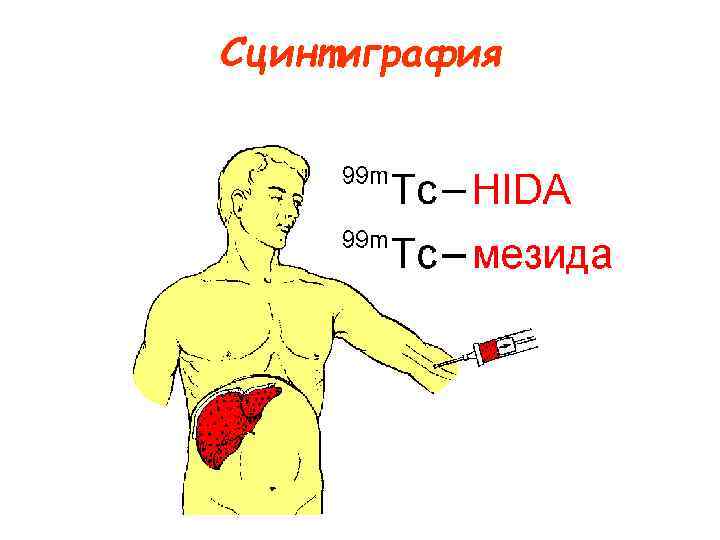

Сцинтиграфия

Сцинтиграфия

Исследование на гамма-камере (сцинтиграфия)

Исследование на гамма-камере (сцинтиграфия)

Сцинтиграфия

Сцинтиграфия